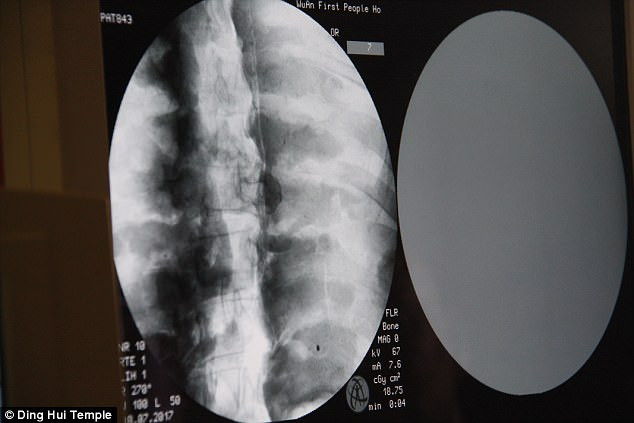

Kết quả chụp CT cho thấy thi hài của thiền sư Ci Xian còn nguyên vẹn đến mức khó tin.

Đặc biệt, hàm trên, răng trên, xương sườn và các khớp của thiền sư Ci Xian vẫn hoàn chỉnh giống như của người mới qua đời.

Điều này cho thấy xác ướp thiền sư Ci Xian ở trong tình trạng rất tốt, không có dấu hiệu bị phân hủy.